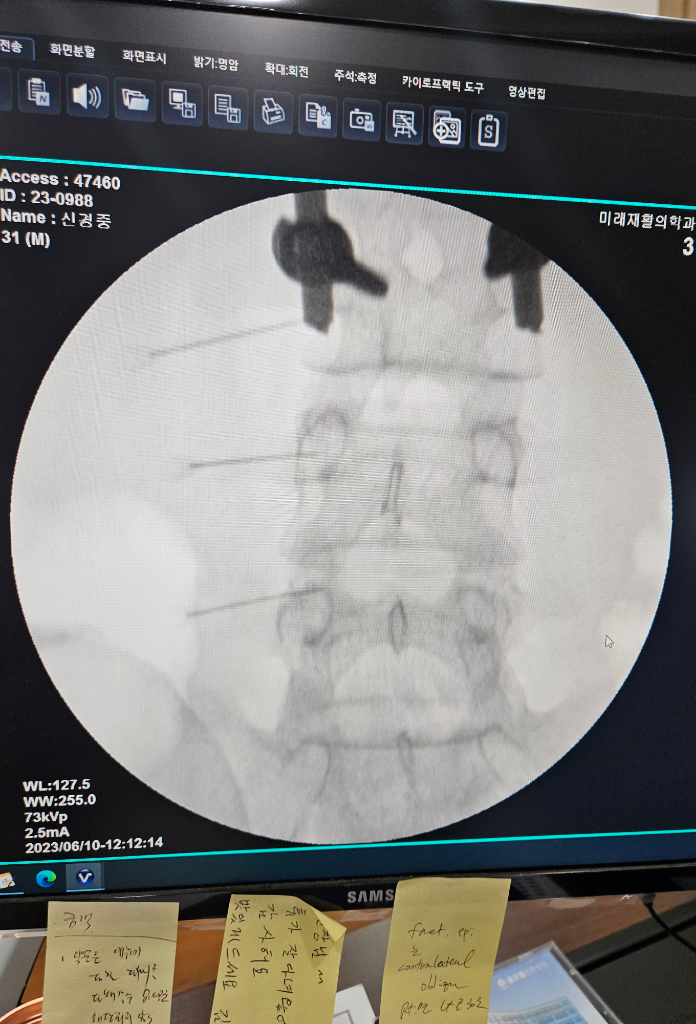

걸을때 엉치통증 있습니다 다리도 땡겨요

안녕하세요. 근무중 앉아서 살짝넘어지고 엉치 골반뒤쪽이 땡겼거든요 순간 그 뒤로 하루뒤 엉치가 땡기고. 왼쪽허벅지도걸을때 땡기네요ㅜㅜ발도 약간 저리구요

토요일 신경주사 맞구 일요일은 휴식하고

월요일에 일을 무리했어요 근데 13일에다친후 이후부터 증상이 일어납니다ㅜㅜ넘어질때 찌릿한게 거기부터인가요?

척추의 신경의 문제로 인한 통증 같아 보이는데 증상이 지속된다면 혈관의 문제는 없는지도 검사해 보시는 것이 좋습니다. 증상이 지속 시에는 현재 다니는 병원 지속적으로 다니며 경막외신경차단주사 치료 및 필요하면 초음파 검사로 동맥정맥 검사를 해서 정맥의 문제로 인한 혈관통증은 아닌지도 살펴 보는 것이 좋을 것 같습니다.